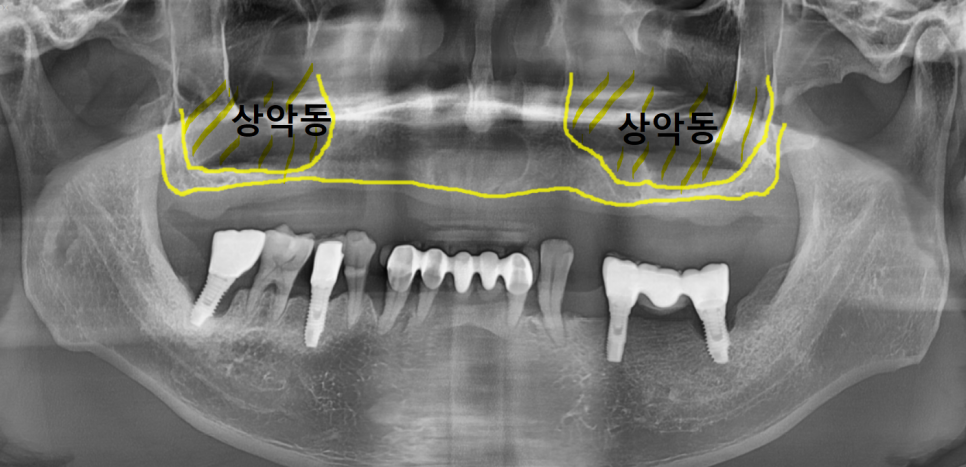

상악동은 위 어금니 바로 위쪽에 위치한

공기주머니 같은 공간으로 얇은 막으로 둘러싸여 있습니다.

사진상에서 보면 이 부위가 상악동인데,

까맣게 보이는 이유는 안이 뻥~ 뚫려 있기 때문이죠.

노란색으로 표시한 잇몸뼈 부분,

눈으로 보기에도 굉장히 얇죠?

이렇게 상악동 안을 뼈로 채워 올릴 예정입니다.